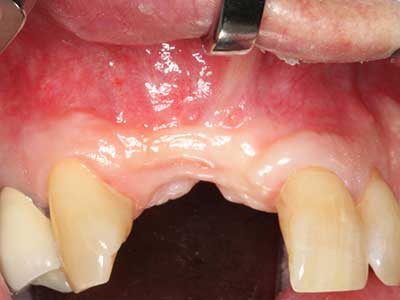

Indikation: Parodontaltherapie

Marginale Parondontalerkrankungen stellen im fortgeschrittenen Alter den Hauptgrund für Extraktionen dar. Sie basieren im Wesentlichen auf einer bakteriellen Besiedlung der Zahnfleischtasche und hierdurch bedingten Entzündung mit konsekutivem Verlust des Zahnhalteapparates. Die Ausbildung subgingivaler Biofilme und Konkremente stellt einen wesentlichen ätiologischen Faktor für den marginalen Knochenabbau dar, so dass ihrer Entfernung eine wesentliche Bedeutung in der Therapie zukommt (Drisko 2014, Plessas 2014).

Zur Behandlung einer marginalen Parodontitis lassen sich eine initiale und chirurgische Therapiephase unterscheiden. Neben der Mundhygieneinstruktion und -motivation sollte in beiden Phasen eine suffiziente Reinigung der Wurzeloberfläche erfolgen, wobei im regenerativen Setting zumeist ein offener Zugang gewählt wird. Die Reinigung der Wurzeloberfläche kann durch die Verwendung spezieller Ansätze auch piezochirurgisch erfolgen, wobei unterschiedlich gebogene Instrumente auch schlecht zugängliche Bereiche wie Furkationen erreichen. Die systemimmanente Wasserkühlung spült dabei die gelösten Konkremente und Bakterien aus der Tasche. Um zusätzlich die Abtragung von Zahnhartsubstanz zu minimieren, wurde bei speziellen Systemen wie dem Piezomed ein Applikations-Feedback eingebaut. Hierbei wird die Abtragungsleistung konsequent reduziert, je mehr Druck auf den Parodontalansatz ausgeübt wird.